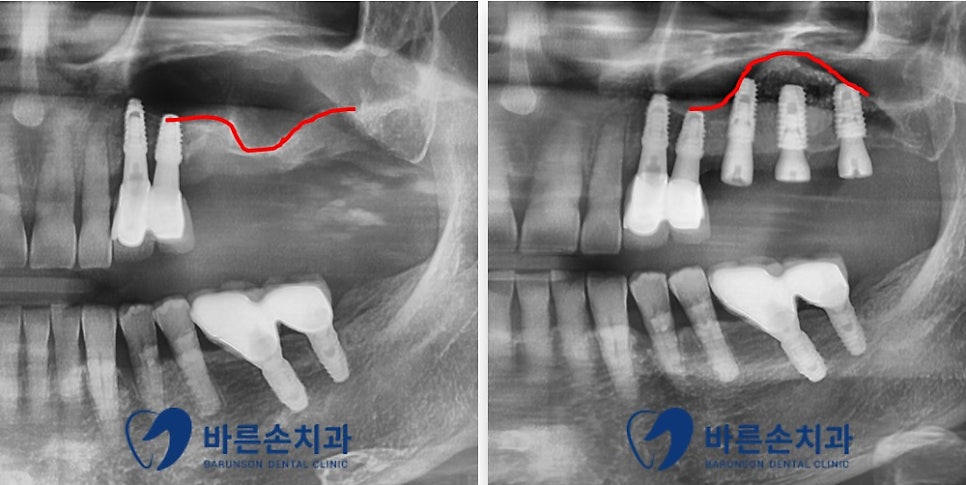

임플란트 식립 완료 후의 모습입니다

위에 말씀드린 것과 같이 상악동 거상술과 치조골 이식을 병행하여

상악동 막이 잘 올라가고

임플란트가 안정적으로 위치된 모습을 확인할 수 있습니다